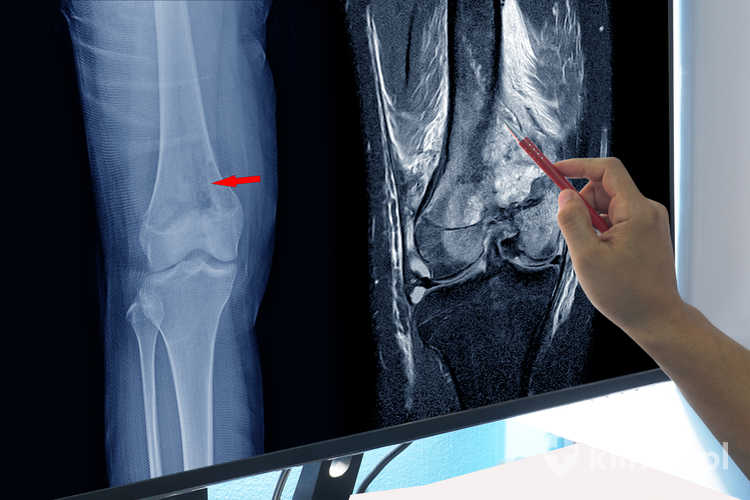

• Rezonans magnetyczny układu kostno-stawowego – główne wskazania obejmują przede wszystkim ocenę zmian pourazowych, zarówno w przypadku stawów dużych (kolanowy, ramienny, biodrowy, skokowy), jak i małych (nadgarstek, śródręcze, śródstopie), w tym również kontrolę stanu ścięgien, więzadeł, chrząstek i obecności płynu. Badanie rezonansem magnetycznym umożliwia diagnostykę uszkodzeń kości (złamań, przemieszczeń, stłuczeń i wewnętrznych obrzęków) oraz zmian zapalnych, martwiczych, zwyrodnieniowych i nowotworowych kości oraz stawów.